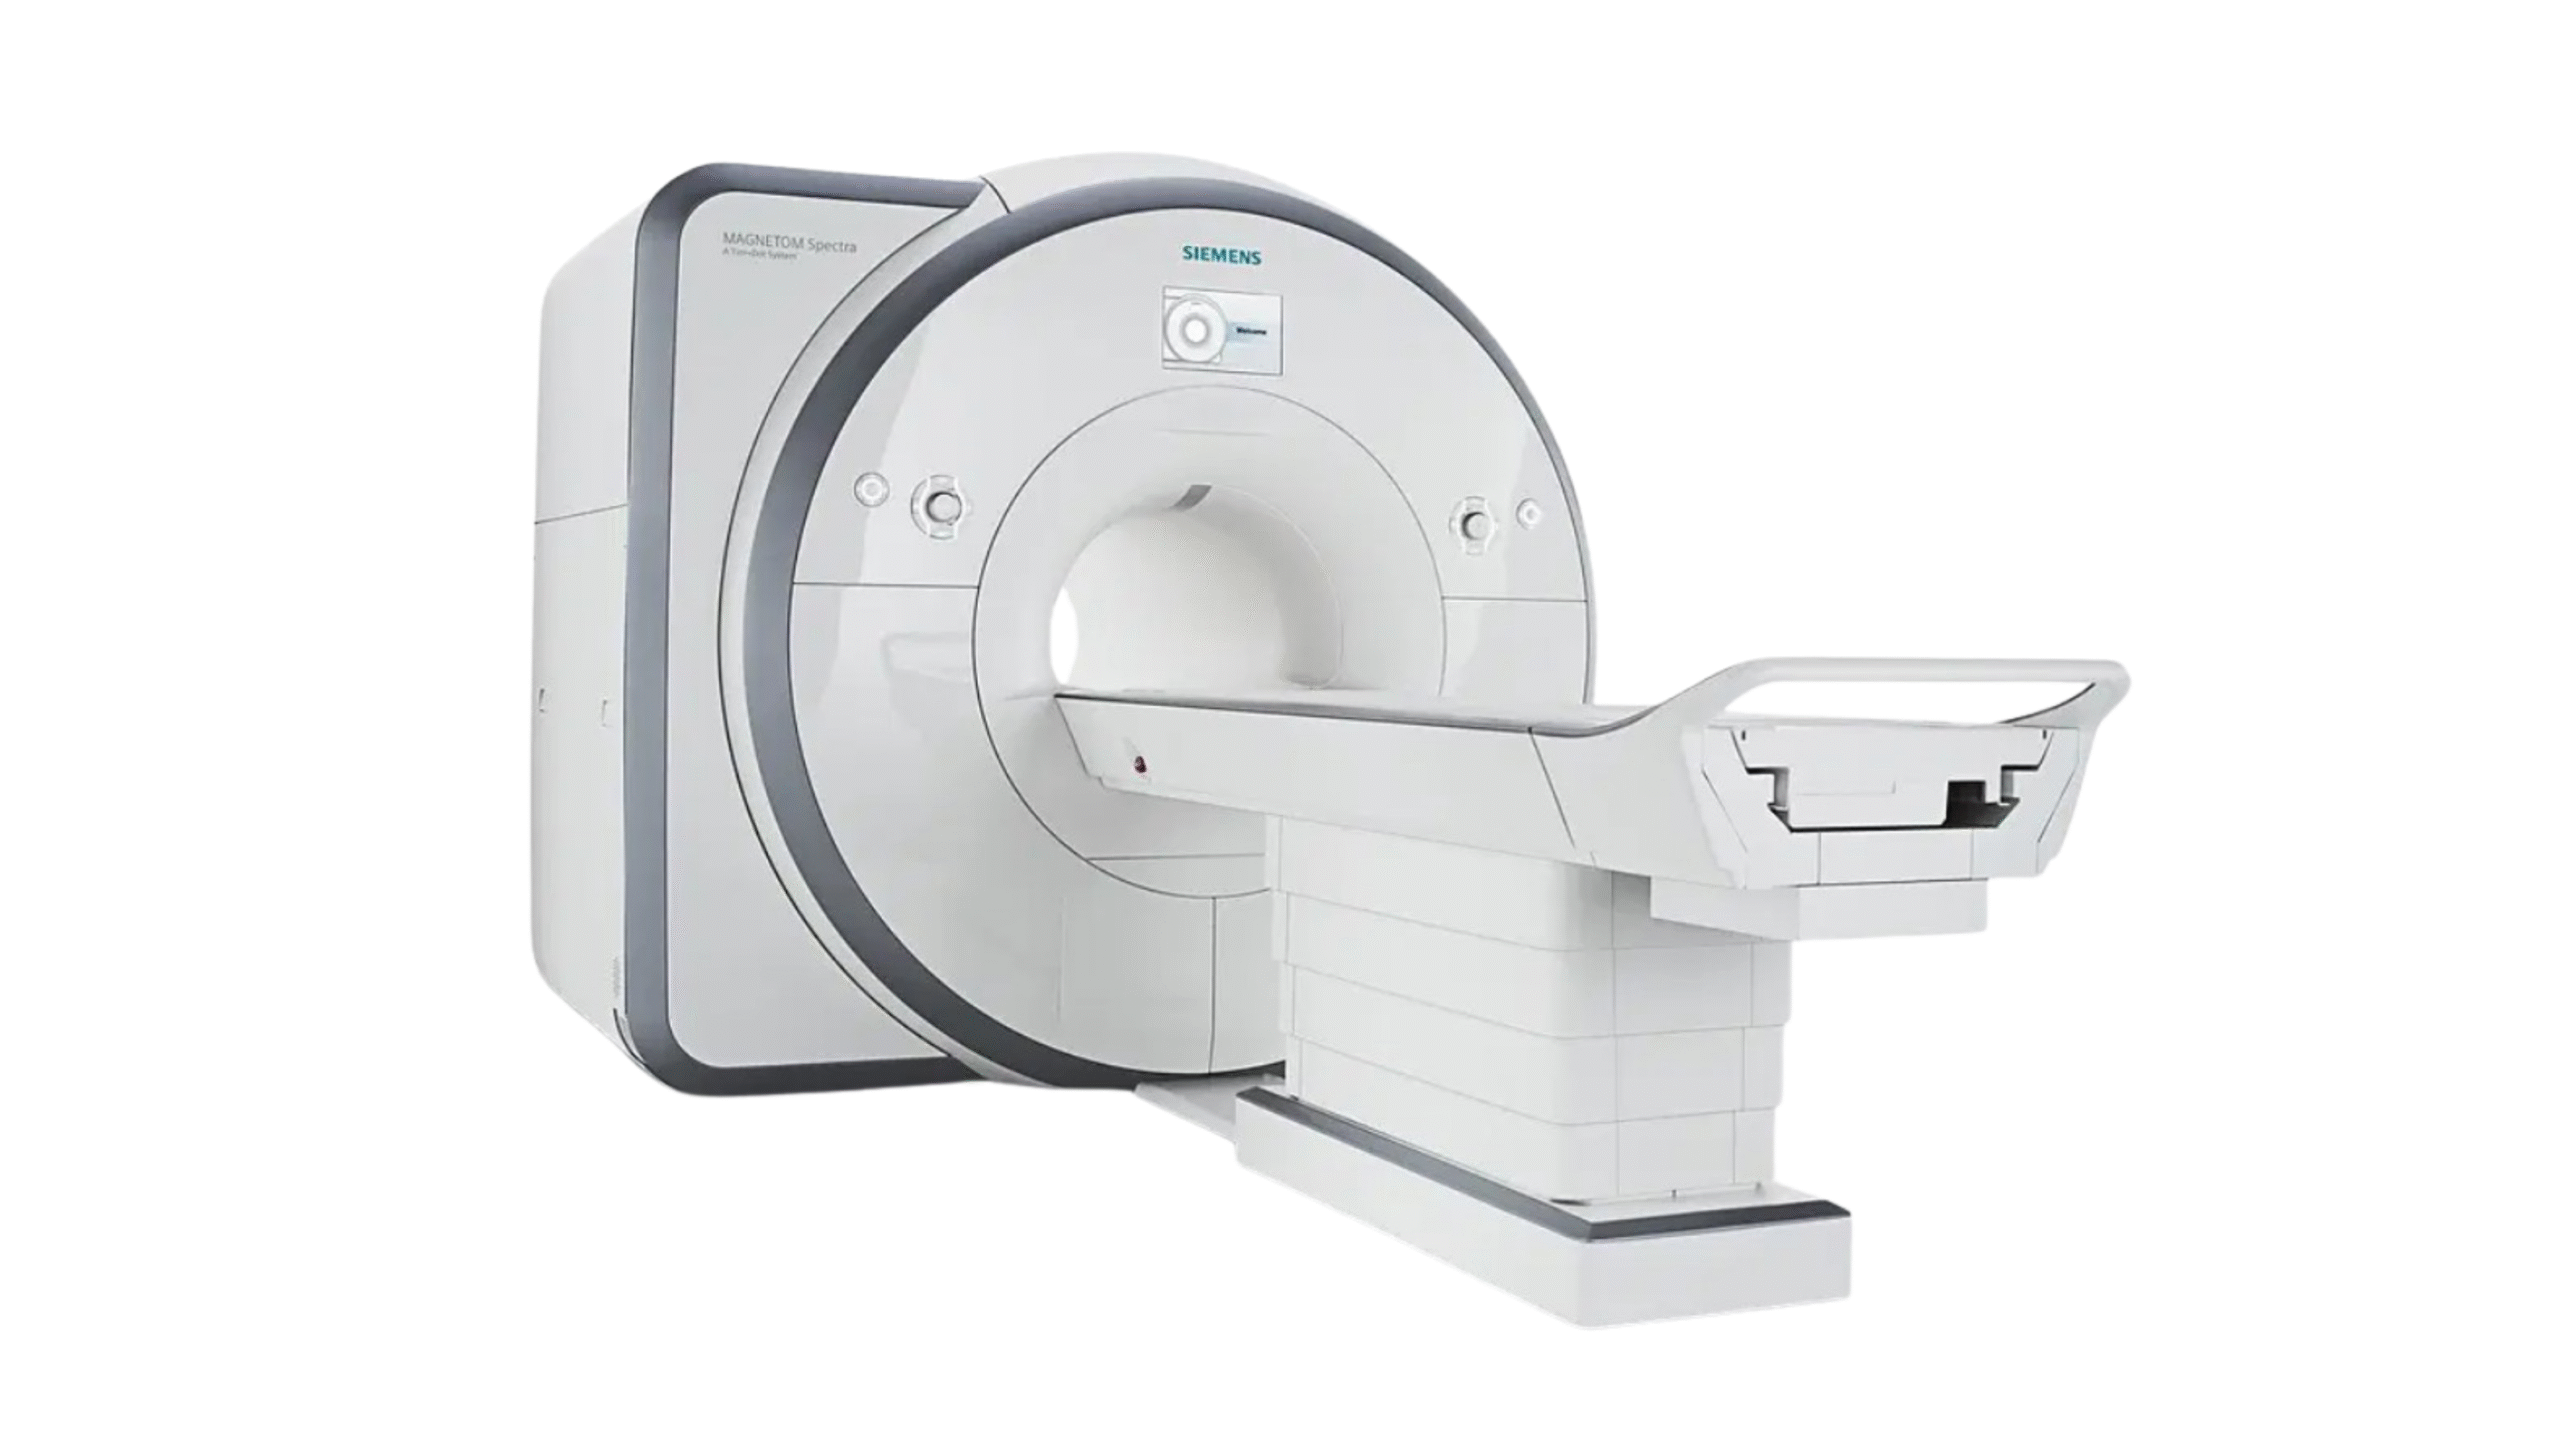

Products